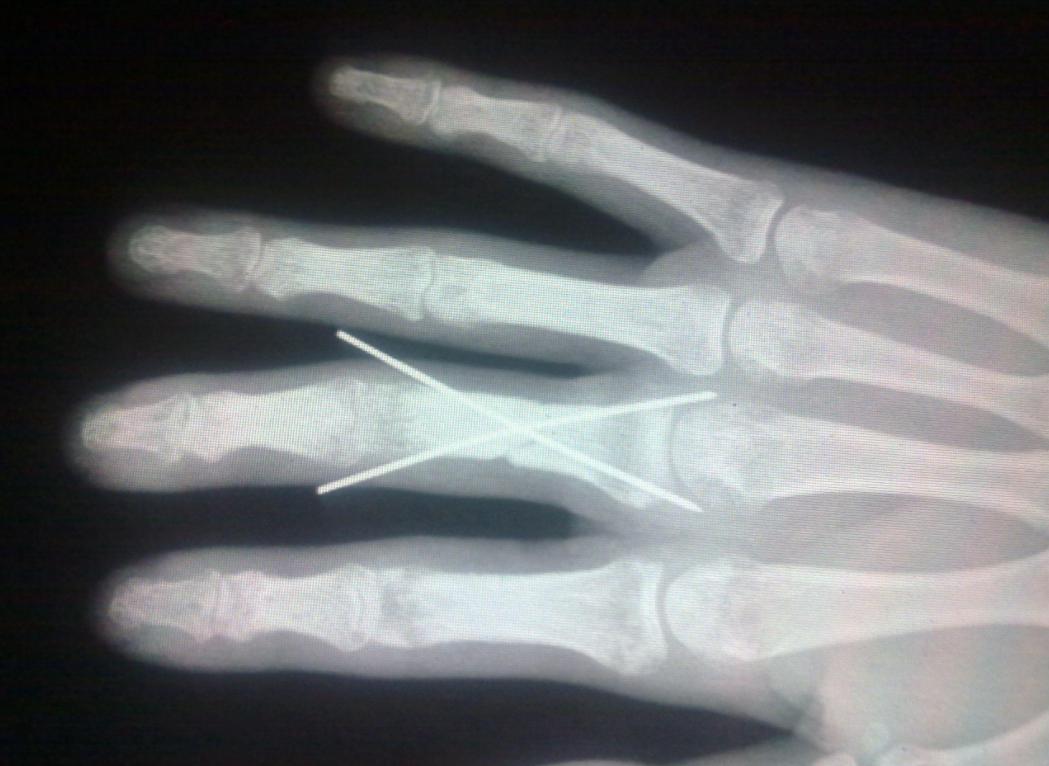

医生检查了新娘的伤情后,告诉他们一个令人心碎的消息: 由于手指被夹得太重,导致血管、神经和肌腱都严重损伤,无法修复。

如果不及时截肢,可能会引发感染或坏疽,危及生命。 他们只有两个选择: 要么保留一个没有任何功能和感觉的残指,要么截去整个食指。

到达医院后,应该按照医生的指示进行检查和治疗。医生会根据伤情判断是否需要进行清创、缝合、固定、接骨、续续指等手术。手术后,还要进行一定的康复训练,以恢复手指的功能和美观。